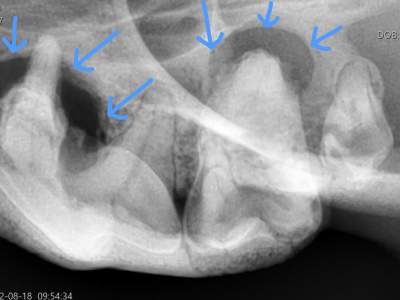

症例1

X線では上顎の骨が溶けてなくなっています。感染源を取り除き顎の骨を守るために上顎全抜歯となりました。

症例2

重度の歯周病により下顎先端の骨がなくなり、左右の顎が外れてしまいました。手足の骨折と違い繋げ合わせたい箇所の骨は既に失われているため、繋げ直すことが出来ません。今以上の骨の喪失を止め、顎の先端を軽量化して生活しやすくするために全抜歯となりました。